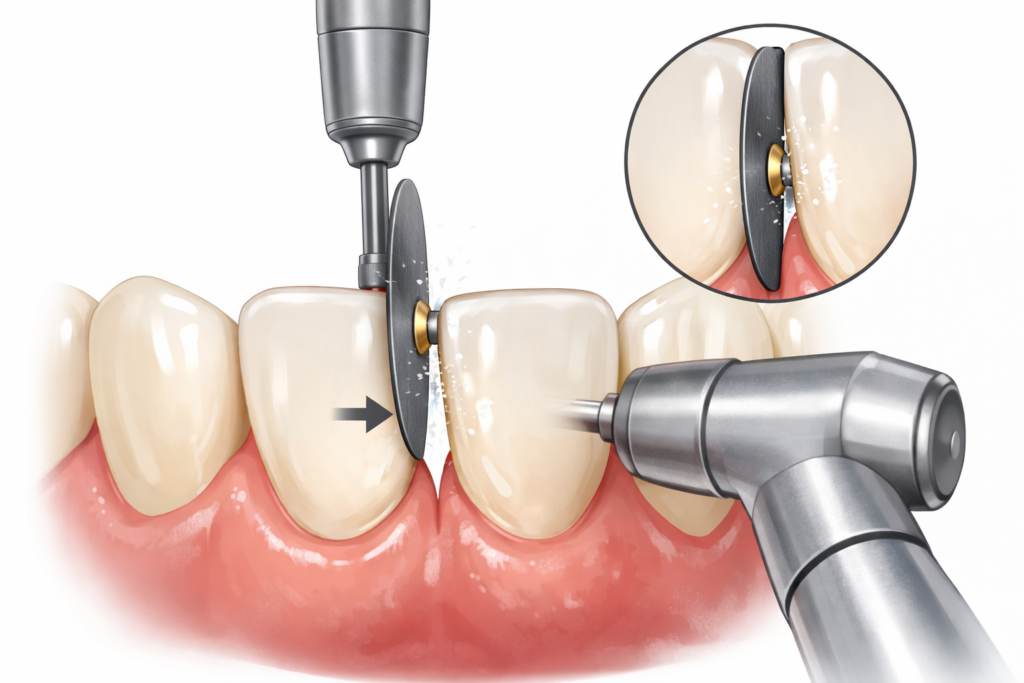

部分矯正で歯を収めるスペースを得たいときに行われる処置が、IPRです。

●IPRとは

IPRとは、InterProximal enamel Reductionという言葉を略した処置で、歯の両サイドを少しずつ削ってスペースを確保する方法です。

歯を削るのは、歯の表面を覆っているエナメル質のところだけほんの少し削るだけですから、歯がしみて痛くなる、歯の形がおかしくなるといった問題はほとんど起こりません。

●IPRの範囲

IPRで歯を削るといっても、エナメル質ならどれだけ削ってもいいというわけではありません。

個人差はありますが、日本人の場合、0.25mmが限界と言われています。

したがって、歯の両側を0.25mmずつ削るとして、1本あたり0.5mmくらいまでのスペース確保が限界となります。

仮に、前歯部6本を部分矯正で整えるとします。

1本あたり、0.5mm削ってスペースを確保するとすると、0.5×6=3mmのスペースが得られる計算です。

見方を変えると、3mm以内のスペースで前歯が収まらないとなると部分矯正では難しいという判断になります。